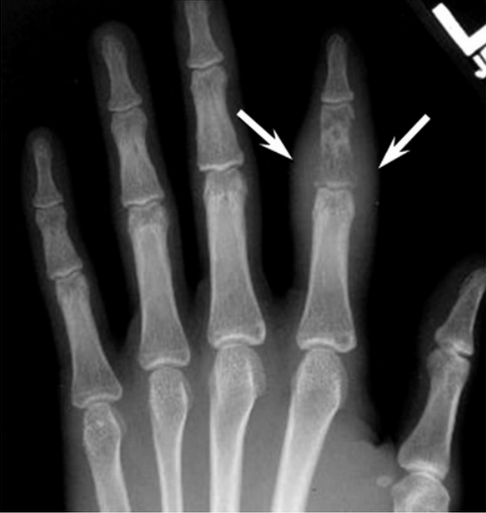

tuberculose osseuse.png